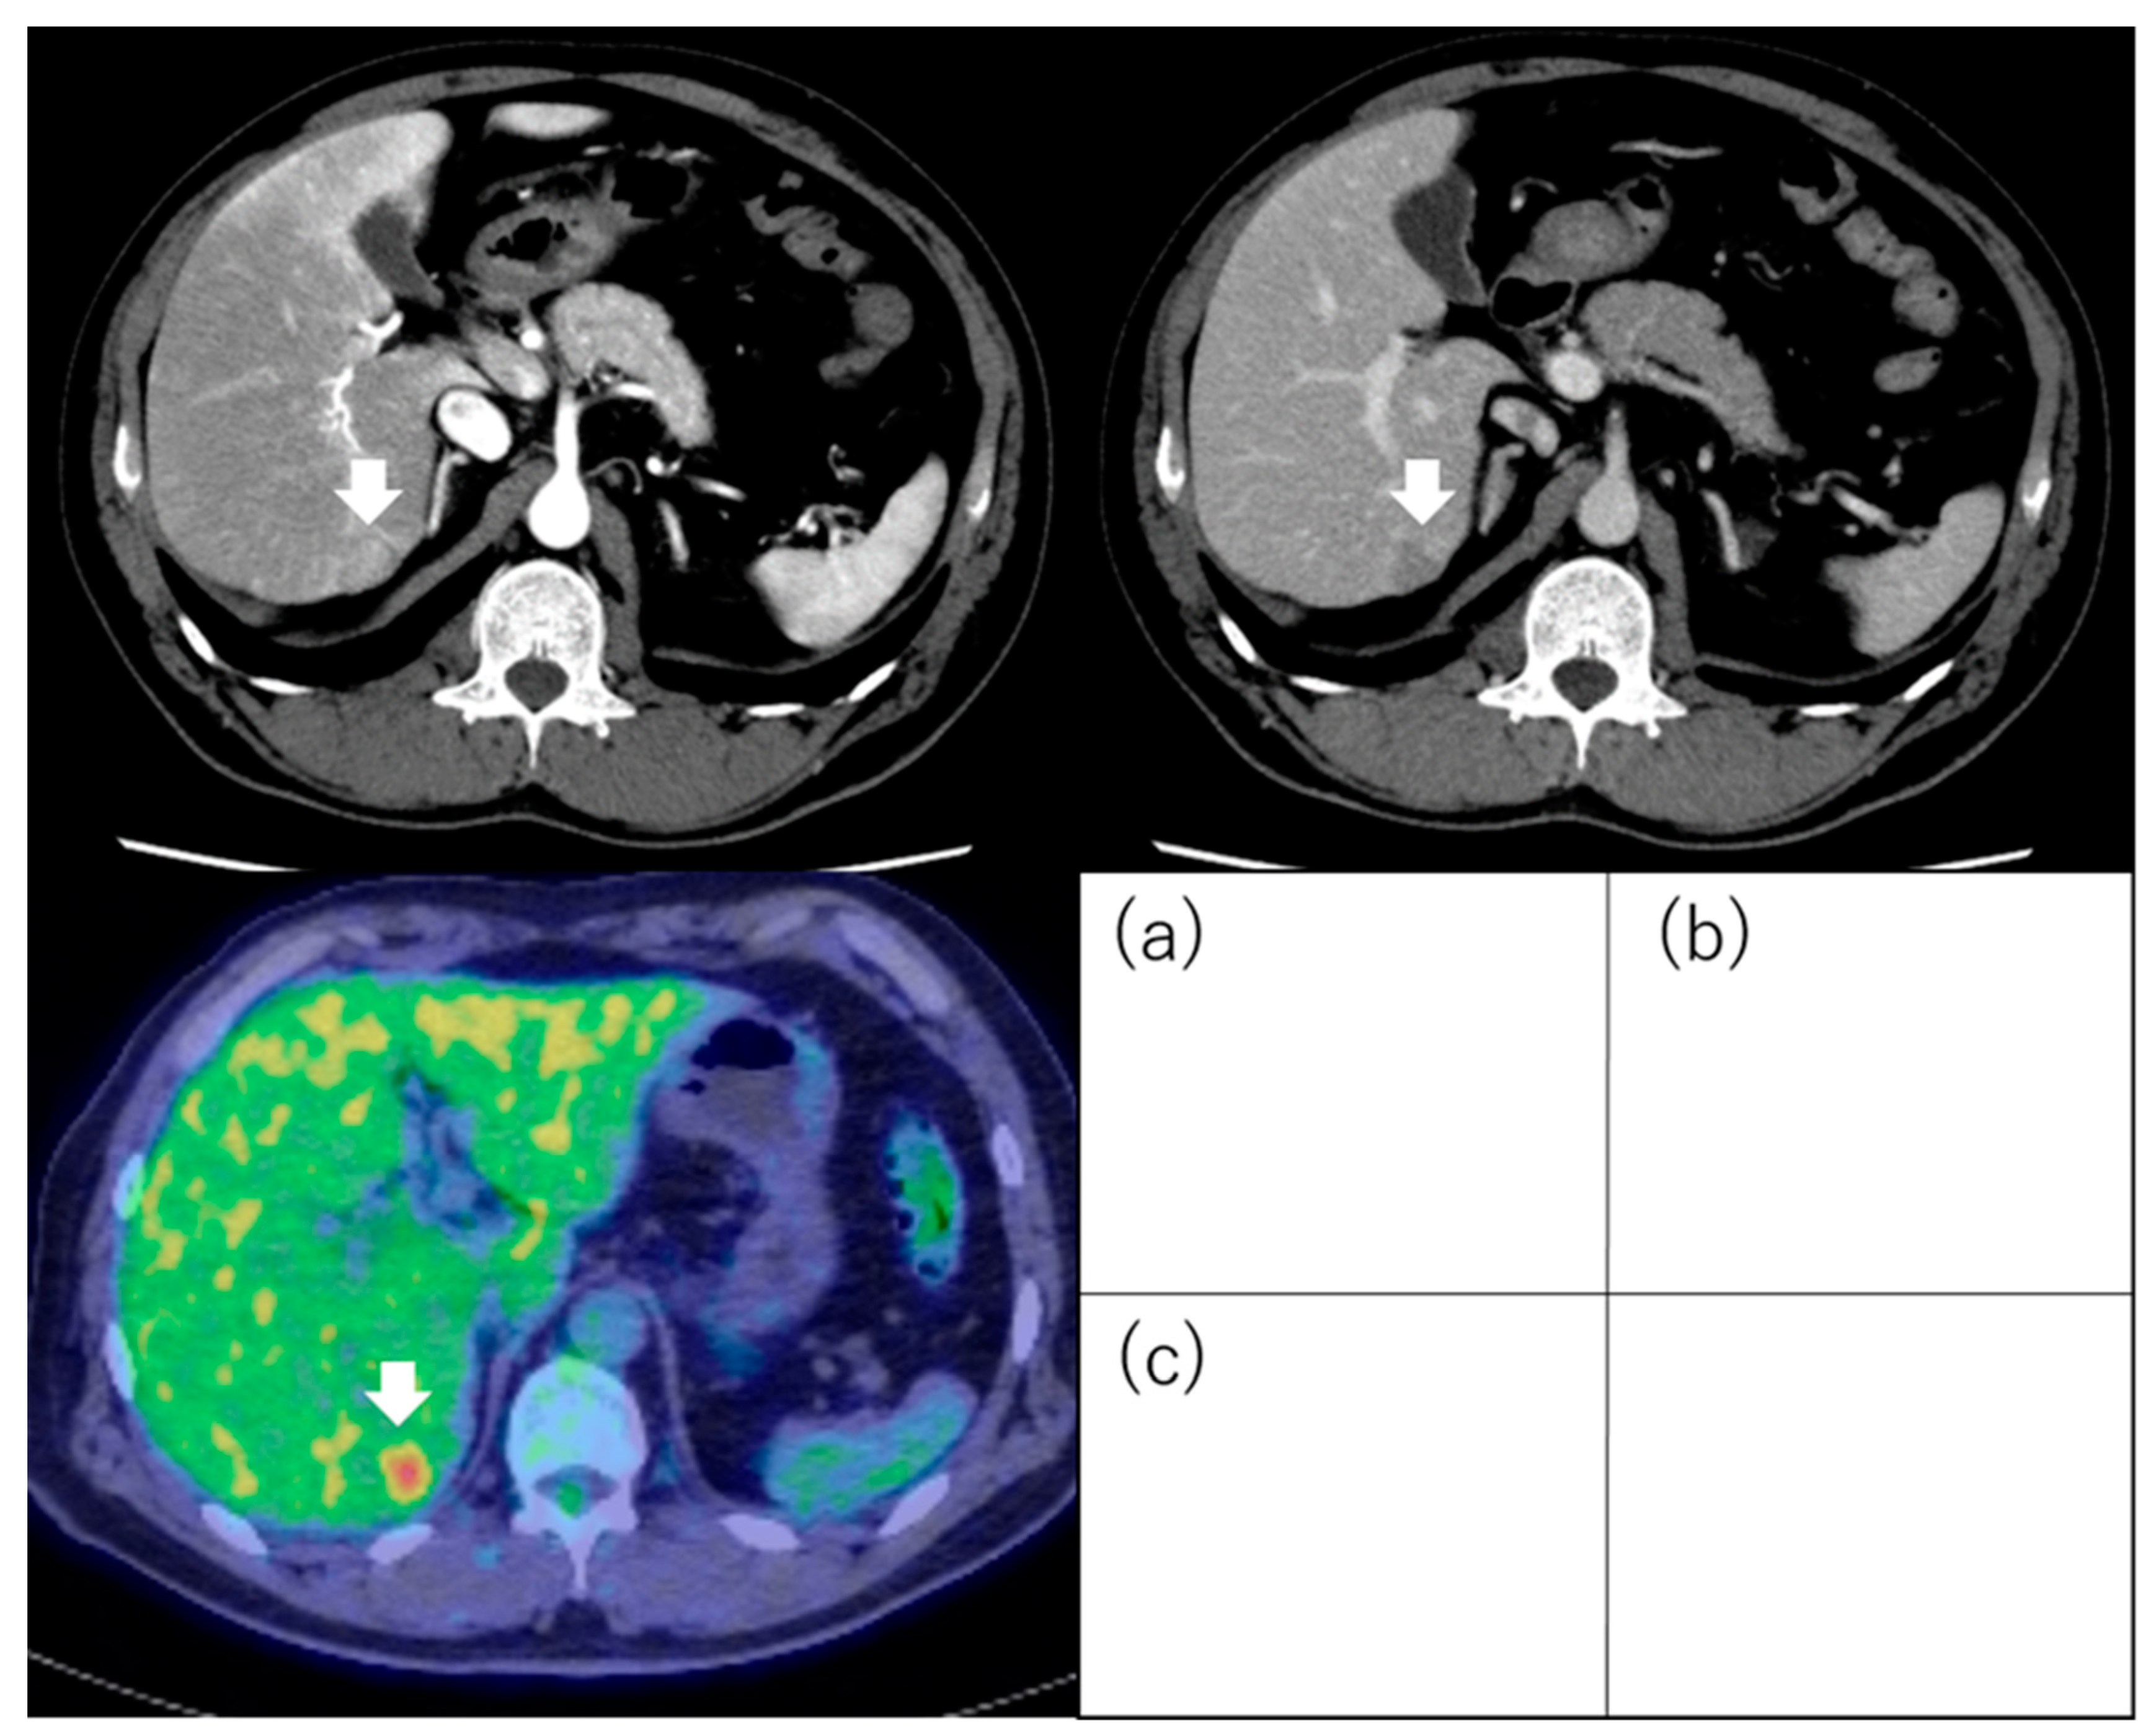

5. 18F-Fluorodeoxyglucose Positron Emission Tomography

5.1. Standardized Uptake Value

5.2. 18F-Fluorodeoxyglucose Uptake

- Hyun, S.H.; Eo, J.S.; Lee, J.W.; Choi, J.Y.; Lee, K.-H.; Na, S.J.; Hong, I.K.; Oh, J.K.; Chung, Y.A.; Song, B.-I.; et al. Prognostic value of 18F-fluorodeoxyglucose positron emission tomography/computed tomography in patients with Barcelona Clinic Liver Cancer stages 0 and A hepatocellular carcinomas: A multicenter retrospective cohort study. Eur. J. Nucl. Med. Mol. Imaging 2016, 43, 1638–1645. [Google Scholar] [CrossRef]

| Lee et al. [75] | 59 | Milan criteria (within/beyond) | LTP | TSUVmax/LSUVmax (cutoff value; 1.15) | Outcome (recurrence) | Significantly difference was seen about recurrence-free survival. TSUVmax/LSUVmax < 1.15; the 1 year and 2 year recurrence-free survival rate was 97% and 97%, respectively. TSUVmax/LSUVmax ≥ 1.15; the 1 year and 2 year recurrence-free survival rate was 57% and 42%, respectively. |

| Detry et al. [76] | 27 | Milan criteria (within/beyond) | LTP | TSUVmax/LSUVmax (cutoff value; 1.15) | Outcome (recurrence, OS) | TSUVmax/LSUVmax > 1.15 was one of the independent factors for recurrence-free survival (HR, 14.4; p = 0.01) and overall survival (HR, 5.62; p = 0.04). |

| Hong et al. [77] | 123 | Milan criteria (within/beyond) | LTP | TSUVmax/LSUVmax (cutoff value; 1.10) | Outcome (recurrence, OS) | TSUVmax/LSUVmax > 1.10 was an independent factor for recurrence (HR, 9.776; 95% CI, 3.557–26.816; p < 0.001). |

| HSU et al. [78] | 147 | “Solitary and ≤6.5 cm” or “≤3 tumors and ≤4.5 cm” and total tumor diameter ≤8 cm | LTP | TNR (cutoff value; 2.0) | Outcome (recurrence) | TNR ≥ 2.0 was one of the independent factors for recurrence (HR, 13.52; 95% CI, 4.77–38.29; p < 0.001). |

| Hyun et al. [79] | 317 | BCLC stage 0 or A | Curative treatment (LR or RFA or LTP) (195) TACE (122) | TLR (cutoff value; 2.0) | Outcome (recurrence, OS) | TLR ≥ 2.0 was an independent factor for OS in curative treatment group (HR, 2.68; 95% CI, 1.16–6.15; p = 0.020). |

| Cho et al. [80] | 56 | Early stage | LR | SUVmax (cutoff value; 4.9) | Outcome (recurrence, OS) | SUVmax was not significant independent factor for recurrence (p = 0.262) and OS (p = 0.717). |

| Hyun et al. [81] | 158 | BCLC stage 0 or A | LR | TLR (cutoff value; 1.3) | Microvascular invasion Outcome (recurrence) | Predictability of TLR for microvascular invasion as follows: sensitivity was 85.5%, specificity was 54.9%, positive predictive value was 63.7%, negative predictive value was 80.4%. TLR was one of the independent factors for metastatic recurrence (HR, 2.43; 95% CI, 1.01–5.84; p = 0.047). |

| Yoh et al. [82] | 207 | Solitary | LR | TNR (cutoff value; 2.0) | Outcome (recurrence, OS) | TNR was one of the independent factors for OS (HR, 1.743; 95% CI, 1.114–2.648; p = 0.016). |